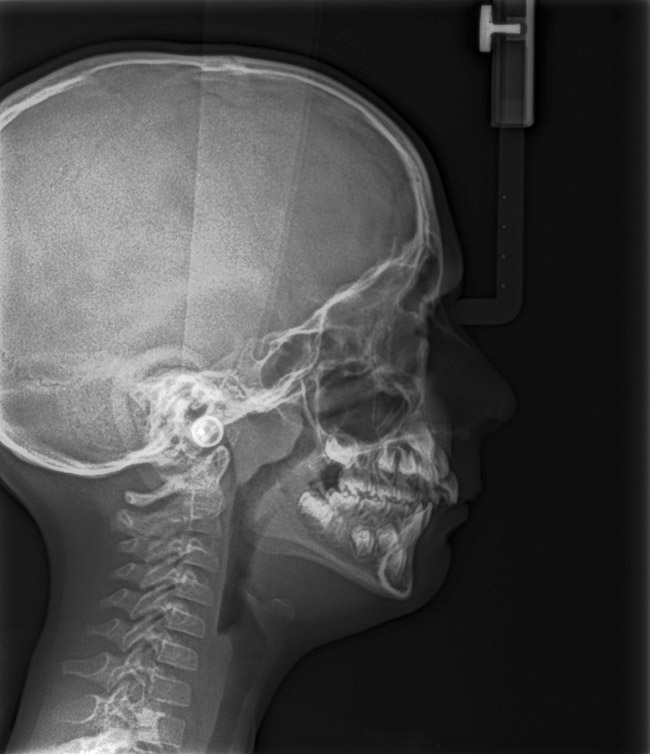

In some children, T&A alone may not completely resolve the OSA (Figure 19 and Figure 20). The longer the airway dysfunction, the greater the structural impact on the airway. An interdisciplinary clinical study54 was conducted on children approximately 6.5 years old with inclusion criteria of OSA, large tonsils, visually constricted airway, and high and narrow palate. Group 1 was treated with rapid maxillary expansion (RME) and Group 2 with T&A. Maxillary expansion has been shown to create improved nasal resistance and an increase nasal cavity volume. In cases without excessive lymphoid hypertrophy, RME can resolve significant levels of OSA.55,56 After the original therapy, only one child had been completely resolved (apnea-hypopnea index [AHI] <1). The remaining subjects switched groups and received the opposite treatment. After receiving both treatments, 29 of the 31 children were cured. It can be concluded that many children must be treated with multiple therapies before resolution, especially if the SDB has previously altered the airway to a significant degree.

(20.) Maxillary anterior tooth wear. Adenotonsillectomy (T&A) performed and postoperative apnea-hypopnea index (AHI) was 6.1. Continued therapy recommended for resolution.

Figure 20